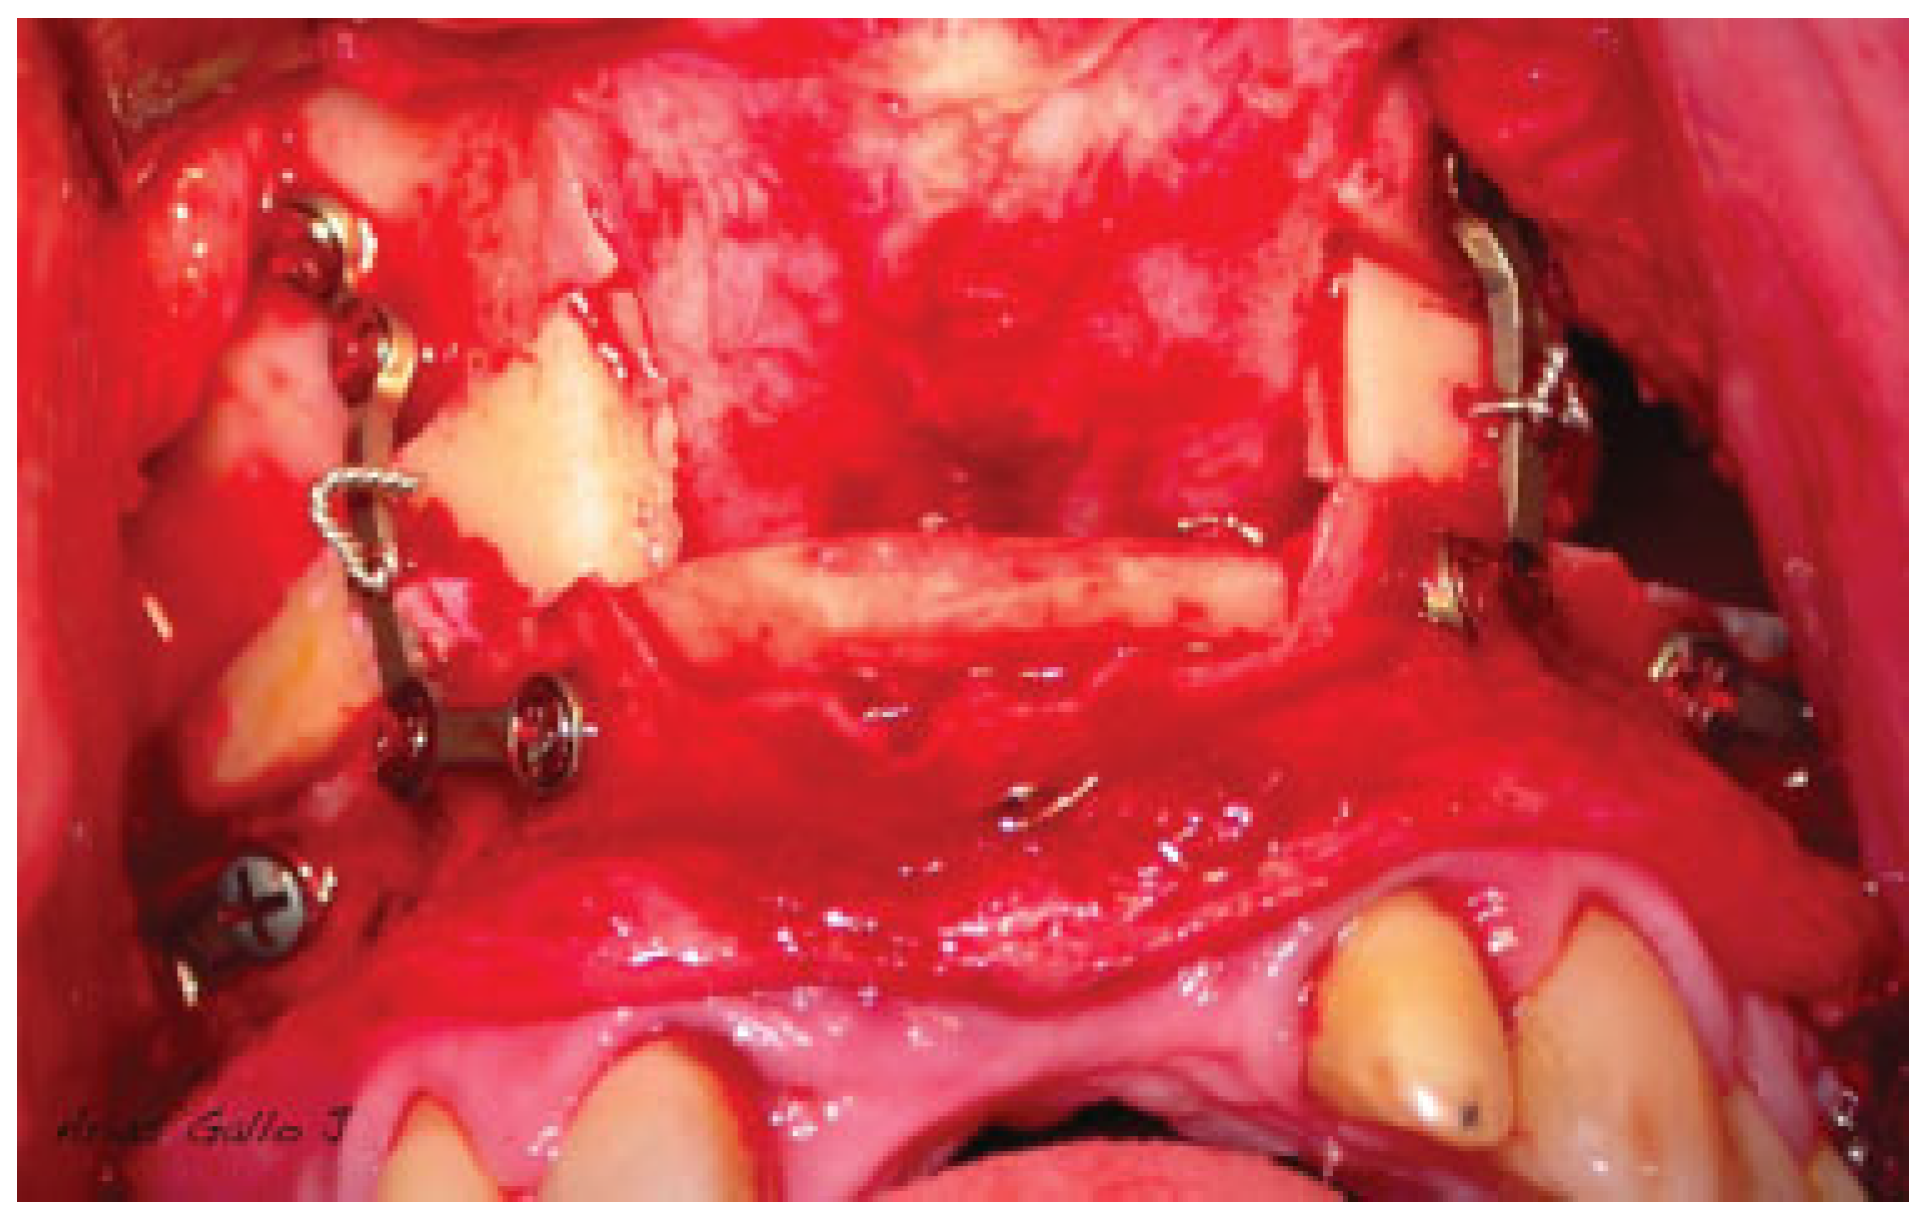

Hereby, we propose a simplified surgical technique with an immediate postoperative positive impact and a promising success rate. Our simplified surgical steps follow. (1) Begin with transposition of the maxillary inferiorly and anteriorly after Le Fort I osteotomy. (2) We emphasize the significance of achieving stable occlusion. (3) Then, we proceed with intermaxillary fixation. The distance of maxilla transportation needs to be planned preoperatively. (4) Next is rigid internal fixation of the dentoalveolar fragment using a customized titanium plate preoperatively. (5) With a tungsten bur, the nasal surface of the maxillary is regularized. (6) Bone grafting blocks are then placed within the gap created by the osteotomy in obtaining the planned vertical height. (7) The bone grafting blocks are fixed in place using a wire that goes beyond the graft and anchors to the custom-made plates (Figure 1 and Figure 2). (8) Finally, check on the maxilla in its new position and new occlusion (Figure 3 and Figure 4). The wire fixation of the grafts allows us to simplify the surgical step of the maxillary repositioning in addition to ensuring the stability of the bone grafts.

Figure 3.

Impaction and fixation of the Le Fort I osteotomy as a conventional procedure. Screw the plates to the fixed maxillary fragment.

Figure 4.

Figure drawing in sagital view. Screw the plates to the fixed maxillary fragment and fixation of the bone block with a wire.